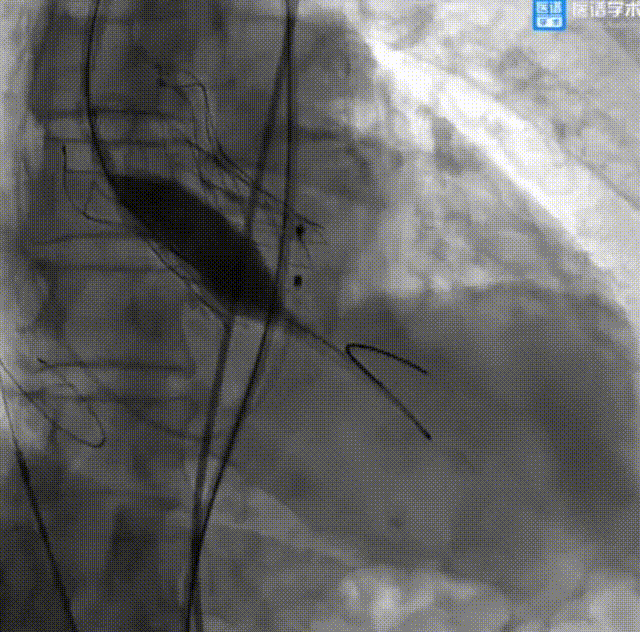

经股动脉主动脉瓣置换术:

球囊后扩

球囊后扩后造影

成功回撤二尖瓣球囊系统和导引鞘后,继续行经股动脉主动脉瓣置换术。术中顺利送入导丝建立入路,导丝成功跨瓣后送入22 mm球囊至主动脉瓣预扩张,后送入TAV27 mm瓣膜至主动脉瓣处。在180 bpm快速起搏的同时释放瓣膜,即刻造影显示中度瓣周漏,遂又送入25 mm球囊至主动脉生物瓣膜处行后扩张,瓣周漏较先前明显减少。术后超声显示平均主动脉跨瓣压差为3 mmHg。